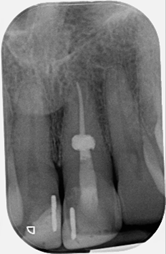

12-Month Healing

6 month review

12 month review

12 month review demonstrating healing

Review radiograph demonstrating healing

12 month review (crown carried out by GDP)

Post-operative X-ray